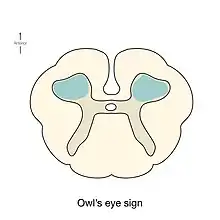

As the non-contrast CT and spine CT angiography are ineffective in imaging modalities, doctors use MRI to confirm the diagnosis. MRI findings, including pencillike hyperintensities on T2-weighted sagittal images and "owl's eyes" or "snake eyes" sign on T2 axial images, indicate the infarction is predominately in the watershed area of the gray matter of ventral horn (anterior spinal artery infarct).[10] Also, posterior paramedian triangular hyperintensity in T2 hyperintensity indicates posterior spinal artery infarct. On a T1 sequence, we may also observe a cord expansion and a decreased signal.[18] However, traditional MRI may show no abnormality especially for those patients in the acute phase.[8] DWI is very sensitive for early detection of spinal cord infarction and shows a typical high signal intensity.[19]